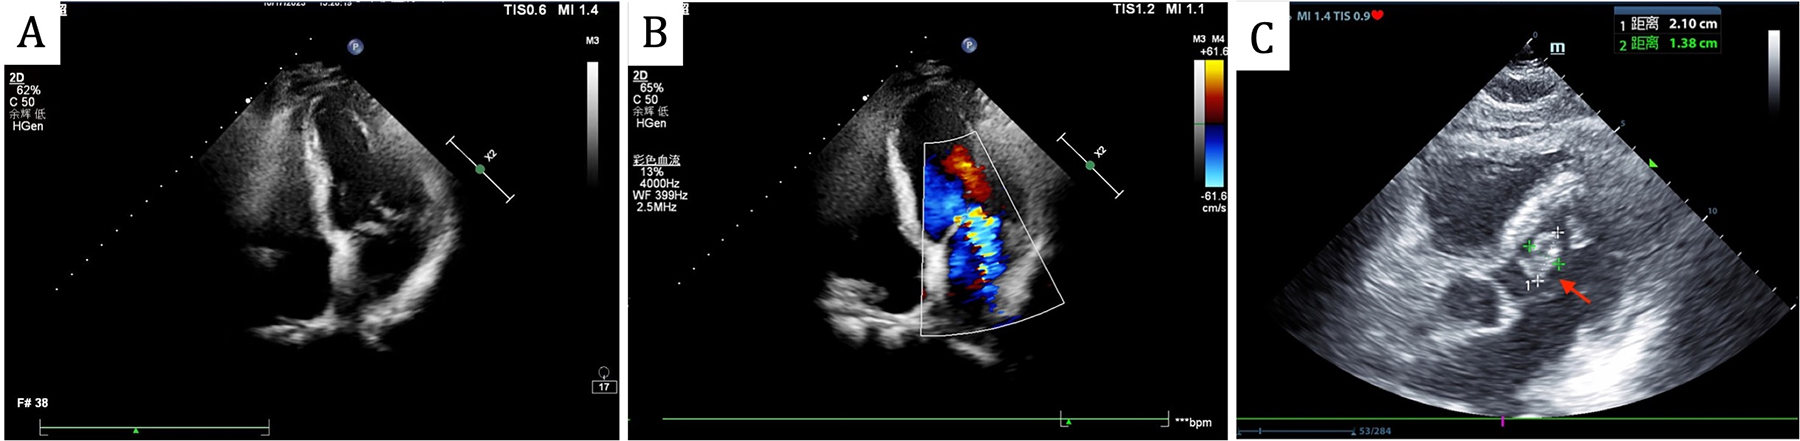

On admission, he had a fever (37.9℃) and a systolic murmur. Lung examination showed coarse breath sounds. Laboratory results indicated elevated white blood cells (11.6 × 109/L), neutrophils (80.9%), C-reactive Protein (11.9 mg/L), Erythrocyte Sedimentation Rate (40 mm/h), and B-type Natriuretic Peptide (674 pg/ml). Echocardiography revealed an Ejection Fraction of 61%, partial “crab-like” movement of the mitral valve's anterior leaflet, and mild to moderate regurgitation (Figures 1A,B). Chest Computed Tomography (CT) showed chronic bronchitis.

Figure 1

Echocardiography revealed partial “crab-like” movement of the mitral valve's anterior leaflet, and mild to moderate regurgitation on admission (A,B), the follow-up echocardiogram revealed a mitral valve mass, as indicated by the red arrow (C).

Head CT showed new hemorrhage in the right basal ganglia (Figure 3). Lumbar puncture and mNGS of Cerebrospinal Fluid (CSF), peripheral blood, and bronchoalveolar lavage fluid were performed. The mNGS results were as follows: 434 sequences of Aspergillus fumigatus in cerebrospinal fluid, 12 sequences of Aspergillus fumigatus in peripheral blood, and no Aspergillus fumigatus detected in bronchoalveolar lavage fluid (Table 1). Subsequent to the mNGS finding, a follow-up echocardiogram was done which revealed a mass on the mitral valve of size 1.38 cm × 2.10 cm suggestive of a vegetation (Figure 1C). Next, voriconazole was initiated to treat suspected Aspergillus endocarditis with embolization and meningoencephalitis. The patient remained comatose, and on the 14th day, with bilateral pupillary dilation and a Glasgow Coma Scale score of 3, the family opted for palliative care. CSF and blood bacterial cultures were negative, and the serum G + GM test was also negative. The G test, also known as the 1,3-β-D-glucan test, detects the 1,3-β-D-glucan component in fungal cell walls. After phagocytes engulf fungi, they continuously release this substance, increasing its concentration in blood and bodily fluids. 1,3-β-D-glucan specifically activates the G factor in Limulus amoebocyte lysate, leading to the coagulation of the lysate. The GM test detects galactomannan (GM), a polysaccharide widely found in the cell walls of Aspergillus and Penicillium species. Galactomannan is released from the tips of fragile hyphae during hyphal growth and is one of the first antigens to be released. The G + GM test is mainly used clinically for the early diagnosis of invasive fungal infections, particularly invasive aspergillosis (6).